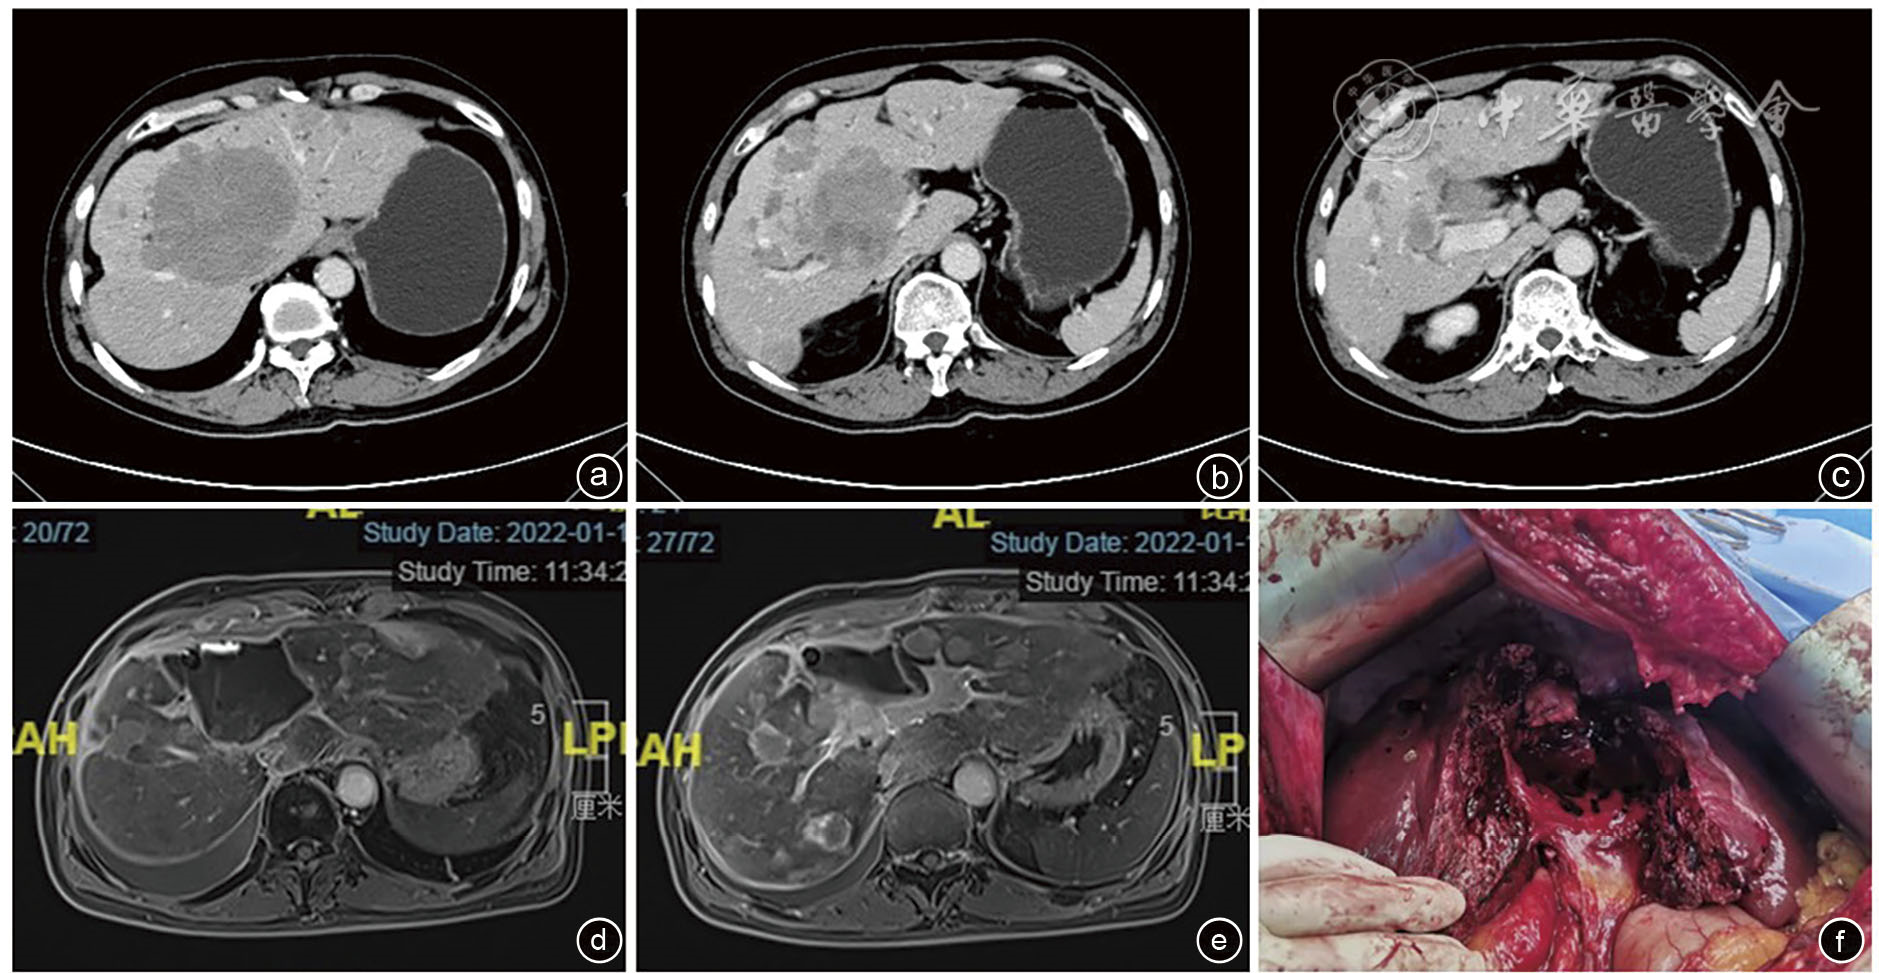

图1 一例NETLM外科减瘤术前术后影像学检查及术中图像 注:a、b、c为术前增强CT,示肝内多发转移灶;d、e为术后增强MRI复查,示减瘤大部分病灶,剩余肝脏代偿增大;f为术后肝脏断面;NETLM为神经内分泌肿瘤肝转移